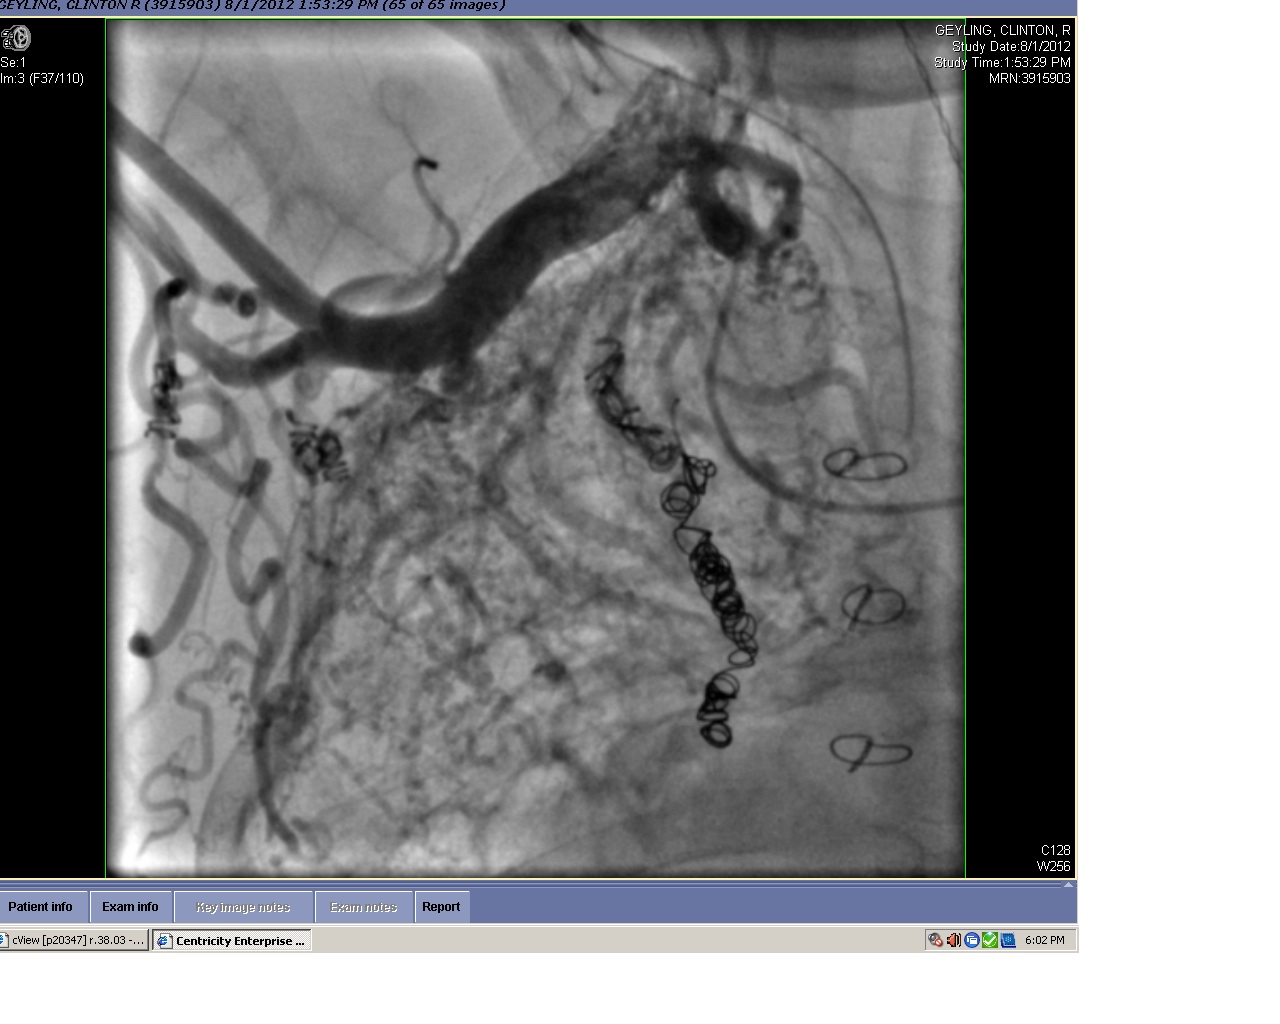

This is a pic of Rudy’s right lung…the thick artery at the top is the subclavian artery and the “springs” are some of Rudy’s coils and the unorganized web of stuff in the middle is a field of collaterals!!!

Rudy is still not a slam-dunk Glenn candidate but Dr. Dan feels like we may have an option to do an adapted Glenn surgery down the road but it would be risky…so we would still need to wait until the risk of NOT DOING surgery outweighs the risk of DOING surgery – the same position we are in now.  So, we’ll continue to wait and pray for a Glenn green light in the future.

Got the call after 6pm and had the consult with the docs. Here’s Dr. Dan giving us the subclavian slideshow. More details will follow but in short: stable & steady progress. Probably no clear-cut plan for surgery at this point.